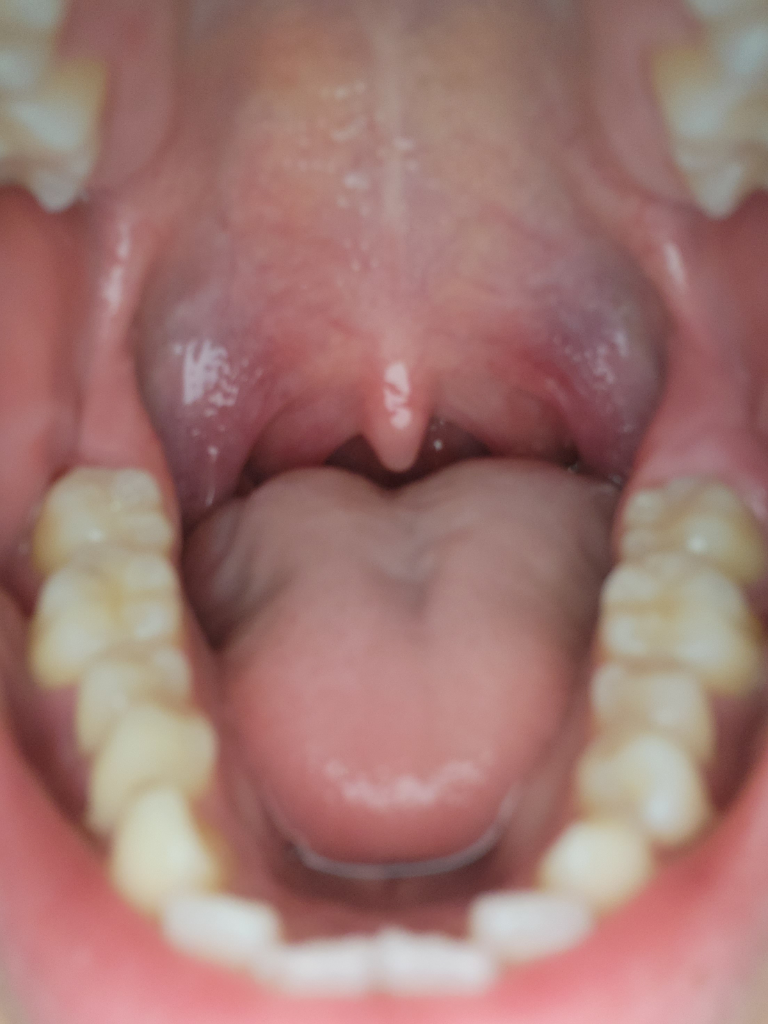

사진보시면 오른쪽 어금니 뒤쪽 잇몸이 어제부터 현재 지금까지 부어있는데 왜이런건지 알고싶습니다.

현재 타이레놀 하나 복용중이고 위쪽치아가 부은 잇몸과 계속 맞닿아있어 약간의 걸리적거림이 있습니다.

• 1번 째 사진